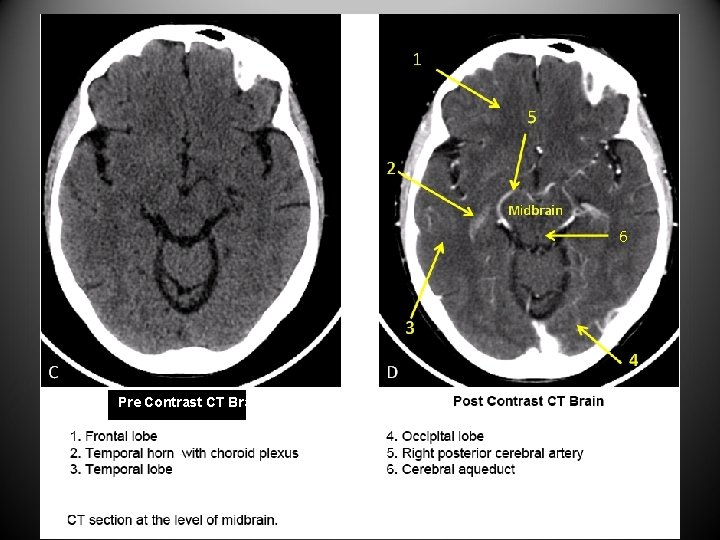

CT Titbits • CT provides axial views of the brain and spine. • Computer reconstructed process can provide sagittal view. • Pre-contrast CT is best for evaluation of bone and acute hemorrhage. • Bone and acute blood appear hyperdense. • Post-contrast CT enables visualization of vasculature and abnormal brain tissue. • Normal brain does not enhance with contrast. • CSF is hypodense and dark. • Vertebra are counted down from C 2 or up from S 1.

6 Pre Contrast CT Brain